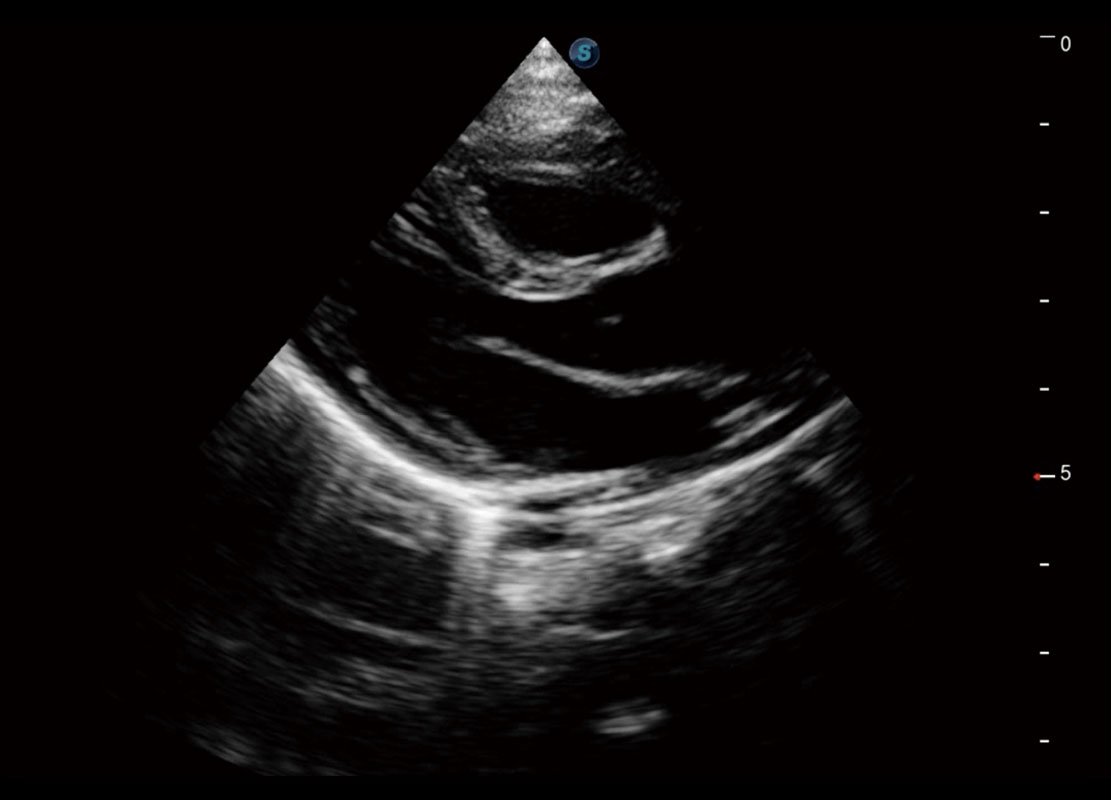

新生儿心脏